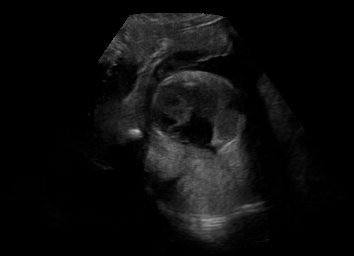

Real in-vivo images. 22 ultrasound sequences were collected using a GE Voluson E8 machine during standard fetal screening exams of 8 patients. Each sequence is several seconds long. We extracted all 4427 frames and resize them to , see Fig. 2 for some examples. The resulting image set was randomly split into training-validation-test sets by a 80-10-10% ratio.